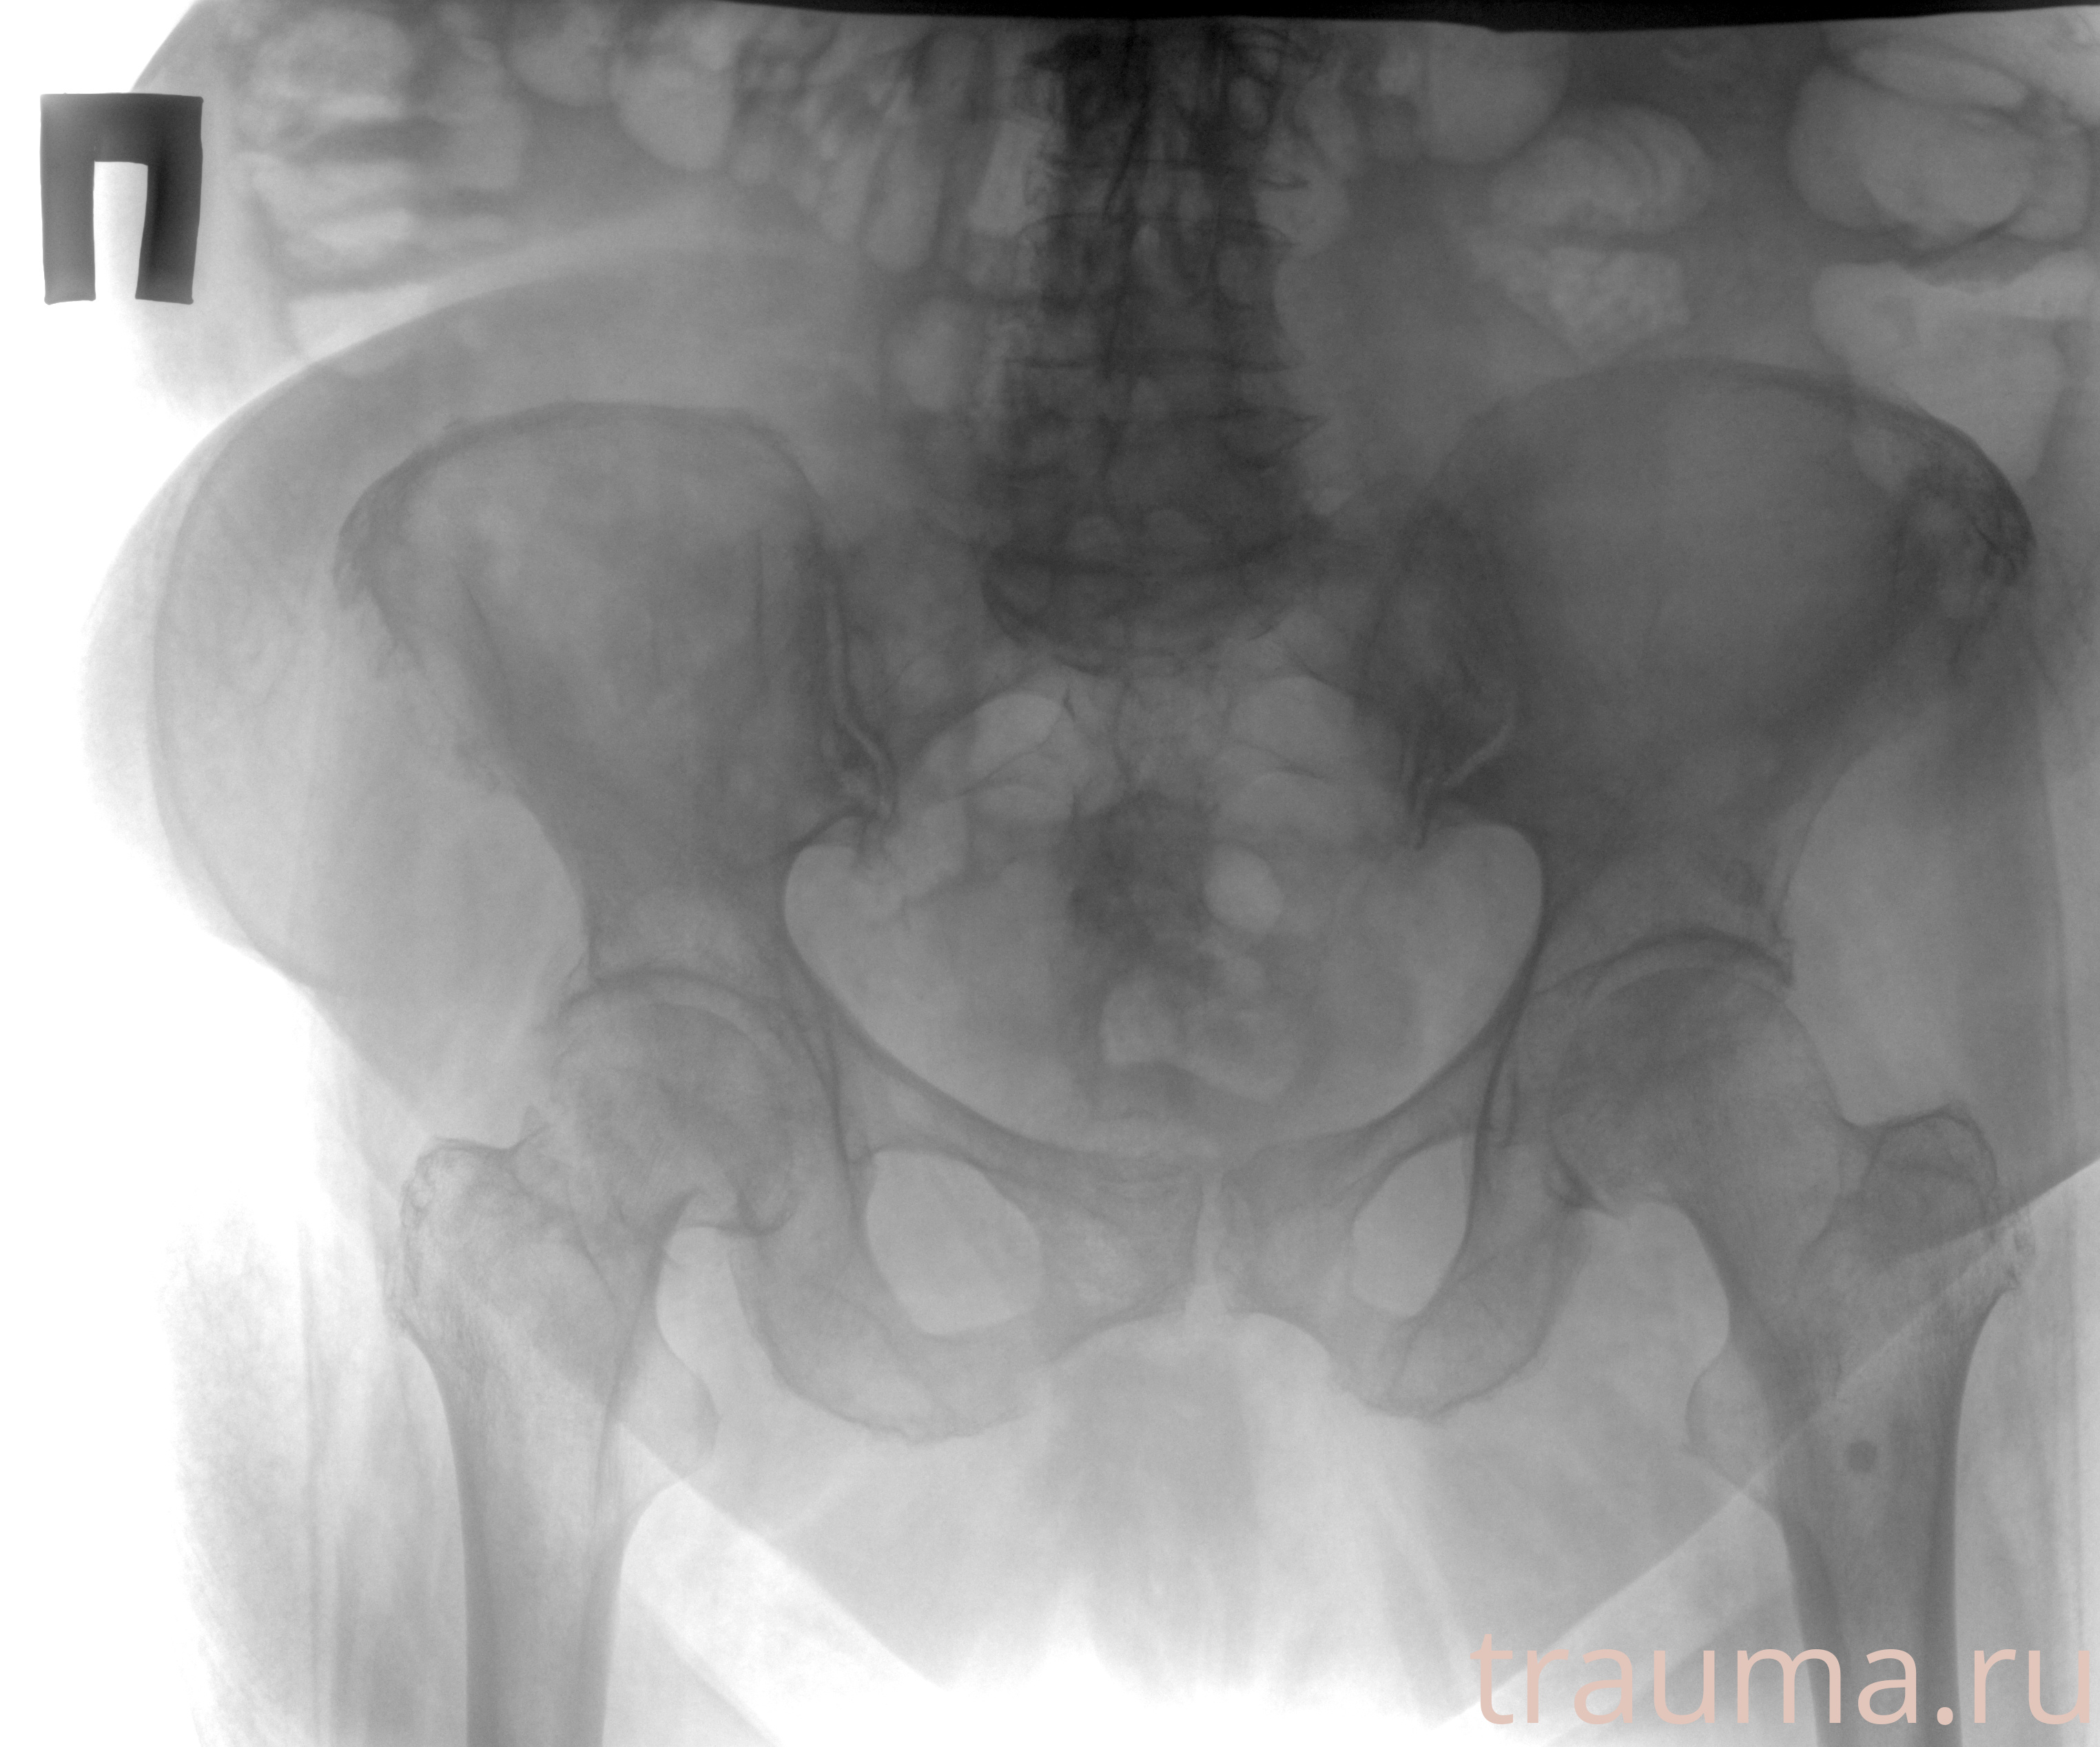

Рентгенограммы

Рентген на дому: по вашему адресу приезжает врач-рентгенолог, травматолог-ортопед с мобильным рентгеновским аппаратом, проводит диагностику травмы или заболевания, делает необходимые рентгенограммы, дает рекомендации по дальнейшему лечению. Получить качественные снимки в домашних условиях возможно благодаря уникальной методике, разработанной МосРентген Центром для института  Склифосовского